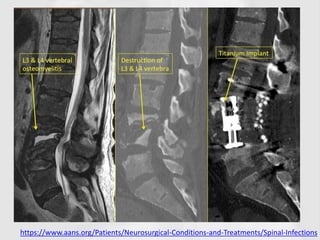

Cont.

• Radionuclide scanning will show increased

activity at the site but this is non-specific.

• MRI may show characteristic changes in the

– Vertebral end-plates, intervertebral disc and

paravertebral tissues;

– This investigation is highly sensitive but not specific.

– Similar features may be seen in discitis.

https://www.aans.org/Patients/Neurosurgical-Conditions-and-Treatments/Spinal-Infections